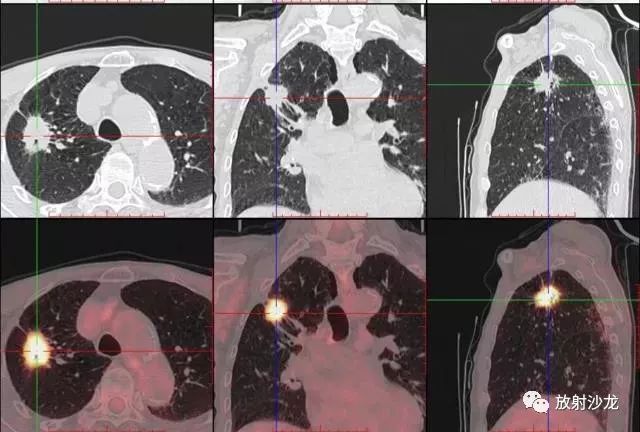

PET-CT是目前世界上最先進(jìn)的核醫(yī)學(xué)分子影像設(shè)備,中文稱為正電子發(fā)射計算機(jī)斷層/X 線計算機(jī)體層成像。

PET-CT等于PET+CT,包含PET(功能分子影像)與CT(解剖影像)的最優(yōu)化組合;即同時具有PET和CT的功能,但它絕不是二者功能的簡單疊加,因為PET與CT優(yōu)勢互補,“1+1>2”。PET-CT除了具備PET和CT各自的功能外,其獨有的融合圖像,將PET圖像與CT圖像融合, 可以同時反映病灶的代謝,可以早期診斷疾病的同時,明顯提高診斷的準(zhǔn)確性。

18F-FDG(氟脫氧葡萄糖)是葡萄糖的類似物,是臨床最常用的顯像劑;18F-FDG能反映體內(nèi)葡萄糖利用狀況。腫瘤細(xì)胞內(nèi)可積聚大量18F-FDG,但是18F-FDG僅僅是葡萄糖類似物,腫瘤細(xì)胞攝取后不能進(jìn)一步代謝,屬于“只進(jìn)不拉”,能在腫瘤細(xì)胞內(nèi)積聚,經(jīng)PET-CT顯像可顯示腫瘤的部位、形態(tài)、大小、數(shù)量及腫瘤內(nèi)的放射性分布。同時腫瘤細(xì)胞的原發(fā)灶和轉(zhuǎn)移灶具有相似的代謝特性,一次注射18F-FDG就能方便地進(jìn)行全身顯像,18F-FDG PET-CT全身顯像對于了解腫瘤的全身累及范圍具有獨特價值。